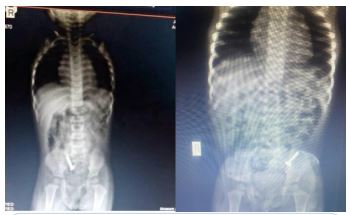

She presented with a plain abdominal radiograph which showed a FB (nail) in the body of the stomach (Figure 1) This was done about 6 hours prior to the presentation at our facility. A repeat radiograph done at the presentation showed the FB (nail) at the region of the terminal ileum (Figure 2). She was commenced on nil per oral, intravenous fluids and monitoring (clinical and radiological). She had two additional plain abdominal radiographs, (Figure 3, 24 hours on admission) and (Figure 4, on day 3). The vital signs remained stable and the abdominal examinations remained equivocal throughout the period of admission. She was discharged following a repeat radiograph which showed no evidence of FB in the GIT.

Figure 3: AP + Lateral view of plain abdominal radiograph. (24 hours admission).